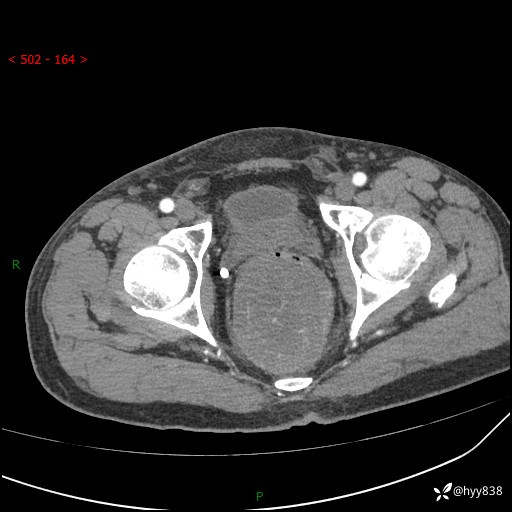

盆腔CT平扫+增强